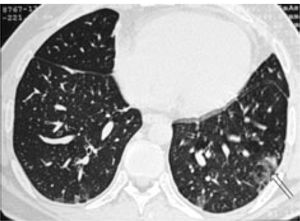

He had positive double stranded anti-DNA (ds-DNA) at 39 RU/mL (normal range: 0-20), positive anti-smooth muscle antibody (ASMA) with titre 1:160 and positive anti-nuclear antibody (ANA) with titre 1:40. His anti-mitochondrial antibodies (AMA) were negative and his Im-munoglobulin G (IgG) was raised only marginally at 17.2 (normal range: 6.0-15.0). A liver biopsy was obtained & showed changes of interface hepatitis with lobular necrosis, cholestasis and pericellular fibrosis while, in the portal tract edges non-caseating granulomas and lymphoid aggregates were present. Due to complaints of chest pain - on a follow-up examination-, a chest radiograph was requested (Figure 1) This x-ray was repeated one month later (Figure 2), while his CT scan findings are shown in figure 3.

LIP is more common in women (average age 55 years) and it has been associated with autoimmune diseases, pulmonary infections, immunodeficiency, serum dysproteinaemias and drug reactions and graft vs host disease (GVHD). Symptoms mostly consist of chronic cough, dyspnoea, weight loss, fatigue and rarely fever while, haemoptysis or chest pain can occur. Few patients (< 4%) are asymptomatic on presentation. Chest x-ray findings include reticular or reticulonodular opacities and to a lesser extend hilar lymphadenopathy, pleural effusions and honeycomb appearance (from extended fibrosis).4,6 High resolution Ctscan images typically show subpleural fibrosis (predominately in basal areas), ground-glass attenuation, traction bronchiectasis and pulmonary parenchymal cysts.3,5